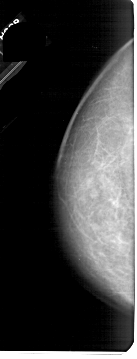

A_1661_1.LEFT_MLO

LEFT_MLO LINES 5491 PIXELS_PER_LINE 2251 BITS_PER_PIXEL 12 RESOLUTION 43.5 NON_OVERLAY